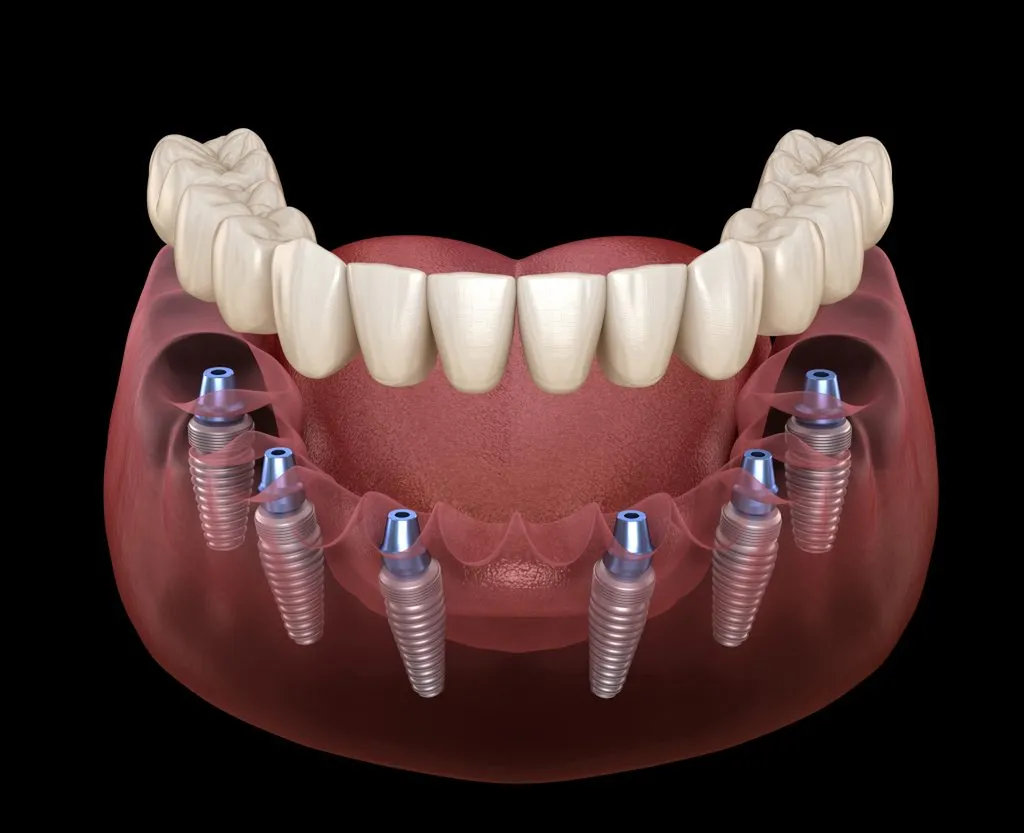

Le principe est identique : il s’agit de soutenir une prothèse dentaire fixe complète (un bridge) sur un nombre minimal d’implants dentaires.

La technique All-on-6 (Tous sur 6) : Cette approche utilise 6 implants par arcade pour une assise encore plus large et une force de mastication optimisée. Elle est souvent recommandée lorsque la qualité et la quantité osseuse le permettent, offrant une robustesse supplémentaire.

Contrairement aux méthodes traditionnelles, la technique All-on-6 consiste à ancrer une prothèse dentaire complète et fixe sur six implants dentaires répartis stratégiquement dans chaque arcade. Cette configuration assure une stabilité biomécanique exceptionnelle, idéale pour une restauration buccale complète.

Via le guide chirurgical, pose des 6 implants en titane avec une précision millimétrique

Durée moyenne : 2 à 3 heures par arcade